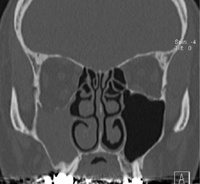

CT

右片側性上顎洞炎

右上顎洞の虚脱

uncinate processの外側への偏位

中鼻道の拡大

眼窩下壁の尾側への偏位;眼窩容積の増大

後方の側頭下窩脂肪の増生

CT冠状断像骨条件表示